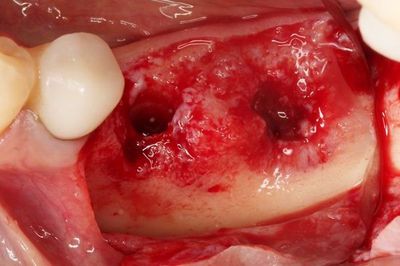

骨欠損部分に自家骨切削片を置きました。

わずかにハイドロキシアパタイトを混ぜて、吸収防止対策をしています。

周囲にはハイドロキシアパタイト(下)とカルシウムフォスフェイト(上)を

生理食塩水で混和したものを填入します。

骨移植材の填入を終えました。